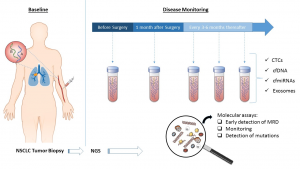

Μάρκου Αθηνά, Επιστημονικός Υπεύθυνος του ερευνητικού έργου με τίτλο: «Υγρή βιοψία ως εργαλείο για την έγκαιρη ανίχνευση της κλινικής υποτροπής»

Ο καρκίνος του πνεύμονα είναι, σε όλο τον κόσμο, η πιο κοινή αιτία θνησιμότητας που σχετίζεται με τον καρκίνο. Ακόμη και μετά την πλήρη αφαίρεση του πρωτοπαθούς όγκου, περίπου 45% των ασθενών με πρώιμο στάδιο NSCLC αναπτύξουν τοπική ή απομακρυσμένη υποτροπή μέσα σε 8-18 μήνες. Αυτές οι μακρινές μεταστάσεις προκύψουν από κυκλοφορούντα-μεταναστευτικά-καρκινικά κύτταρα μπορούν να επιβιώνουν στην κυκλοφορία του αίματος-ανεξάρτητα από τον πρωτογενή όγκο- και έχουν την δυναμική να δώσουν νέες απομακρυσμένες μεταστατικές εστίες.